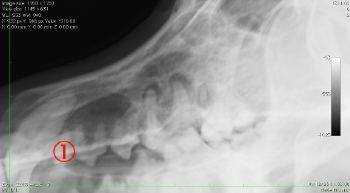

● 歯の破折 3 : 根先膿瘍の放置による目の下の開放創

この3枚の写真に示されるように①は根先部に膿瘍が認められます。②は膿瘍部分に黄色く色づけをしてみました。③は逆サイドの正常な写真になります。![]()